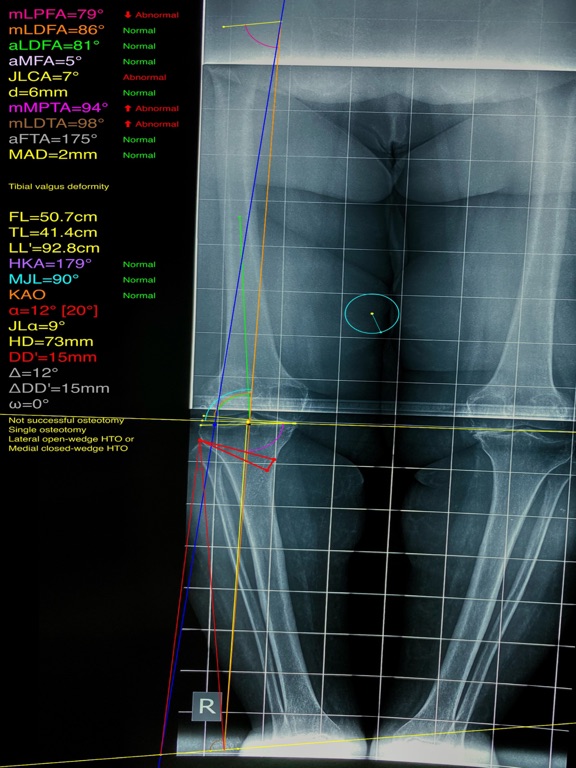

Mal alignment of the hip, knee, and ankle leads to premature cartilage damage and to development of degenerative arthritis of knee joint. Femoral and tibial osteotomies around the knee are established procedures for the restoration of the physiological load distribution of pressure at the knee joint. Accurate preoperative planning is mandatory to avoid under correction or overcorrection of axes or placing the joint-line in obliquity that ends to insufficient postoperative alignment.The majority of osteotomies are still planned and performed using conventional techniques drawing over transparent papers, cumbersome measurements etc.

-mechanical axis deviation (in mm) MAD, anatomical and mechanical femoral axes angle (aMFA),mechanical lateral proximal femoral angle (mLPFA), mechanical lateral distal femoral angle(mLDFA), joint line convergence angle (JLCA),mechanical medial proximal tibial angle (mMPTA), Mechanical lateral distal tibial angle (mLDTA), Hip Knee Ankle line (HKA) ,Mid joint line (MJL) orientation.

-objectively the deviation or deformity in the frontal plane (varus or valgus) and differentiate the level of deformity (femoral and or tibial origin) and according to measured angles objectively suggest where indicated, medial or lateral, open or closed-wedge distal femur osteotomy or high-tibial osteotomy or double osteotomies  and avoiding unwanted obliquity of the joint line

-change the planned mechanical axis to pass at the preferred percentage (Fujisawa point) after evaluation of the residual cartilage thickness left on the involved compartment.

-evaluate in real time the success of intended osteotomy by evaluating the kinematic alignment of the knee (KAO), avoiding residual joint obliquity or malalignment.